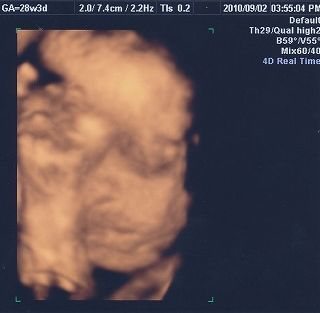

11月11日(木)に出産して、13日(土)から母子同室開始。 今までは、Håkichiの授乳以外は寝るかテレビを見るかだけだったんだけど、同じ部屋にHåkichiがやってきて、Håkichiの観察が勢いを増します(笑) この時に一緒にでる声がまた可愛い♪ なぜか手が異様に白いんですけど・・・・・マミーとダディがほどよくミックスされてるならいいんだけど、パーツごとに違うのは怖いのでやめてください(汗) そして予定日より2週間ほど早くこの世界に出てきたHåkichi。本人はまだ私のお腹の中にいると思っているのか、自然に壁の方に移動していって側面にタッチ。 Håkichi、何度ベッドの中央に戻しても、側面目指して移動し、手と足だけにとどまらず、顔までくっつけてました。 HåkichiはJ君によって非常にコンパクトにまとめられました。 さてここから、新米マミー&ダディにより子育てが始まるわけなんですが、退院した当日は家に帰って何をしていいか分からず、とりあえず2人で観察。 そして翌日。おむつ交換、授乳以外のほかに新たな試練が!! そう、沐浴です。沐浴指導は退院前日に1回やったのみで、まるで自信なし。しかも私たちが実践しようとしている沐浴は普通の沐浴とは違うし・・・ ベビーバスを購入するに当たって、一般的なものは1ヶ月くらいで使わなくなってしまうというのを聞いていたので、私たちが選んだのは ↓ ↓ ↓ ↓ Tummy Tub (←公式ウェブサイト) 「ママのお腹にいた時と同じ、赤ちゃんがいちばん落ち着ける姿勢で沐浴できる」というコンセプトが気に入り、プラス私とJ君が普段からシャワー浴しかしないので、Håkichiをお風呂気分にさせてあげるのはこれが一番かなと思い購入。2歳頃まで使えるらしいし、数年後Håkichiが巨大化しこのタブが使えなくなったら、他の使い道がありそうだし。 という事で、Håkichiをタミータブに入れてみたんだけど、Håkichiがあまりにも小さくてタブの中に埋もれてしまいそうになりパニクる+ブチ切れるJ君。仕方がないので、私がキューバにいた時に足浴に使っていたたらいを使用。 何も知らないHåkichiは幸せそうにお湯に浸かってます。 お湯に浸かっているときはいいんだけど、その後が大変! Håkichiをタオルに包みキッチンのシンクからリビングへ移動し、服を着せるんだけど毎回のように大泣きするHåkichi。数日がこの繰り返しで、移動の最中に泣き始めていることを発見してからは、キッチンにハイローベッド(これもまた優れもの!!)を置き、そこでササっと着替えることに。すると大泣きすることもなくなりました。ほっ。こうやって試行錯誤しながら親になっていくんですね~。 そして新米マミー&ダディのドタバタ劇に付き合わされ、疲れ果てた(?)Håkichiは再び天使のような顔で眠りにつくのでした。 Håkichi、君は本当によく寝る子で母さん嬉しいよ☆ ※ちなみに新生児時代にお蔵入りになったTummy Tubですが、もうすぐ4ヶ月になるHåkichiには大活躍!! その様子はまた後日お知らせします。 |